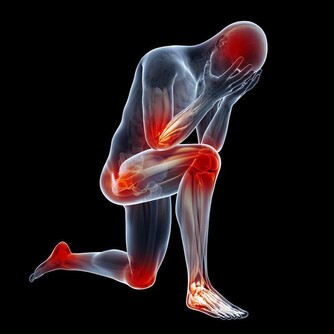

血液循環不好的症狀

1、麻木

麻木和抽筋是血液循環不好的最初症狀。

可以在手足觀察到這類症狀,特別是腿部。

在過度活動後腿部變得過於疲勞和疼痛。

解決這一問題的方法之一是坐著或睡覺時抬高腿部,以減輕疼痛。

此外,血液循環不好還會造成身體某些部位紅腫。